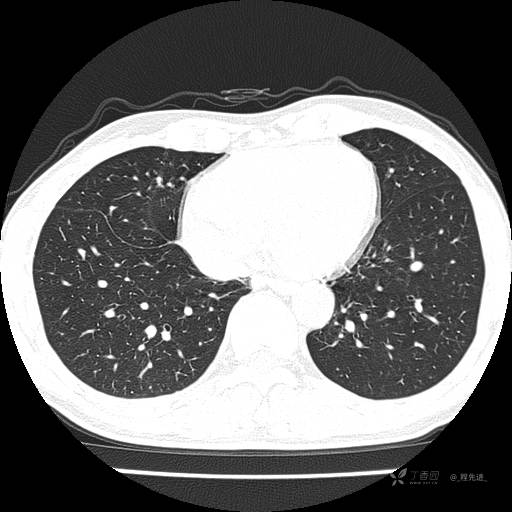

2月特别精彩病例|咳嗽、咳痰20余天,典型病例分享【结果已公布】

患者年龄:51岁

主诉:咳嗽、咳痰20余天

简要病史:20余天前开始出现咳嗽、咳痰症状,阵发性刺激性咳,白色粘痰,不易咳出,无发热,无咯血,无恶心、呕吐等不适,未诊治,咳嗽、咳痰症状持续存在。

体格检查:T:36.3 ℃ P:79 次/分 R:20 次/分 BP:128/64 mmHg,神志清楚,呼吸平稳,双肺呼吸音粗,右下肺闻及细湿性啰音。心率79次/分,节律整齐,各瓣膜听诊区未闻及病理性杂音。腹部未见异常,双下肢无水肿。

辅助检查:我院门诊胸部CT示:如下。心电图:窦性心律;正常心电图。